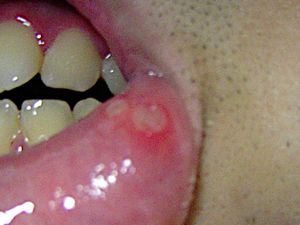

경증 아프타성 궤양은 가장 흔한 형태의 아프타성 궤양으로, 전체 사례의 약 80–85%를 차지한다.[20] 3~10mm 크기의 작은 궤양이 주로 입술, 뺨 점막, 혀의 측면, 구강 바닥 등 비각질화 점막 표면에 발생한다.[20][3] 궤양 주위에는 노란색 내지는 회색빛 홍반이 동반되며, 하얀색 또는 잿빛을 띤다. 극심한 통증으로 인해 음식 섭취나 칫솔질 등이 어려워 일상생활에 지장을 주지만, 10일에서 14일 내에 흉터 없이 자연 치유된다.[3] 1년에 6∼7회 정도 재발하는 경향을 보인다. 소 아프타성 궤양(MiAU) 또는 소 재발성 아프타성 구내염(MiRAS)이라고도 불린다.[15][20]

경증 아프타성 궤양은 가장 흔한 형태의 아프타성 궤양으로, 전체 사례의 약 80–85%를 차지한다.[20] 3~10mm 크기의 작은 궤양이 주로 입술, 뺨 점막, 혀의 측면, 구강 바닥 등 비각질화 점막 표면에 발생한다.[20][3] 궤양 주위에는 노란색 내지는 회색빛 홍반이 동반되며, 하얀색 또는 잿빛을 띤다. 극심한 통증으로 인해 음식 섭취나 칫솔질 등이 어려워 일상생활에 지장을 주지만, 10일에서 14일 내에 흉터 없이 자연 치유된다.[3] 1년에 6∼7회 정도 재발하는 경향을 보인다. 소 아프타성 궤양(MiAU) 또는 소 재발성 아프타성 구내염(MiRAS)이라고도 불린다.[15][20]2. 2. 중증 아프타성 궤양